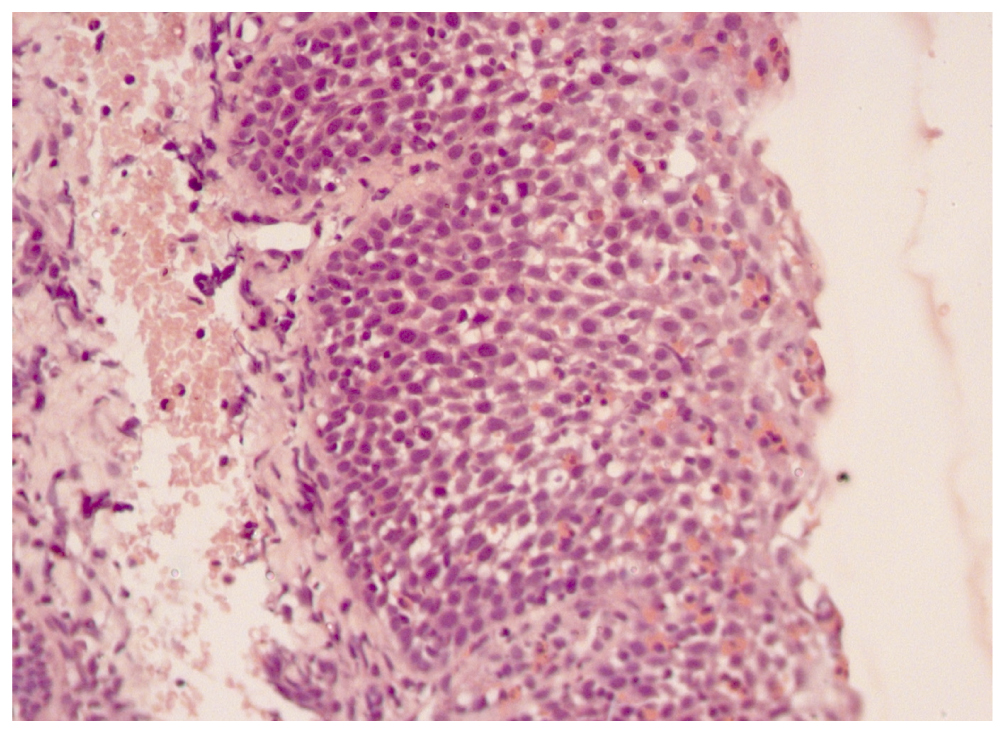

При повторном обследовании через 2 месяца ― эндоскопическая картина с положительной динамикой; биопсия не проводилась, учитывая малый временной промежуток, прошедший со дня первого исследования. Курс лечения топическим ГКС составил 6 месяцев. В общем анализе крови в течение 1,5 лет прослеживалась эозинофилия (11,1–13–9,1–12–6,2–10,0%), в феврале 2016 года впервые содержание эозинофилов в периферической крови соответствовало возрастной норме (4,2%). Сохранялся очень высокий уровень общего IgE в сыворотке крови (489,7–1091,0–452,7–567,8–1039 МЕ/мл) при снижении уровня антиел изотипа IgЕ к белкам коровьего молока. Ухудшения при динамическом наблюдении не наблюдалось, в том числе после отмены топического ГКС и на фоне расширения диеты. Повторная биопсия и морфологическое исследование проведены через год после отмены топического ГКС. В контрольном биоптате слизистой (18.02.2016) микроскопическая картина вернулась к гистологической норме, что является подтверждением эффективности терапии (рис. 2).

Рис. 2. Гистологическая картина слизистой оболочки пищевода через год после терапии топическим глюкокортикоидом.

Fig. 2. Esophageal mucosa 1 year after the end of therapy with topical glucocorticoid.